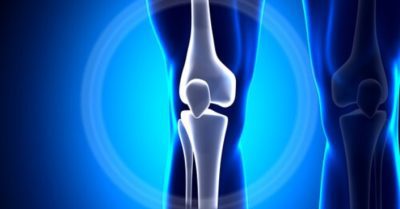

One of the primary benefits of MSM is joint support. Regular supplementation can help reduce joint discomfort, improve flexibility, and support overall mobility.

It is particularly beneficial for athletes, active individuals, and people experiencing age-related joint stiffness.

MSM also has anti-inflammatory properties, helping to decrease oxidative stress and support recovery from physical activity or minor injuries.

By reducing inflammation, it may contribute to better muscle function, improved endurance, and enhanced overall wellness.

In summary, MSM is a versatile supplement that promotes joint health, reduces inflammation, supports connective tissue integrity, and contributes to overall mobility and vitality.

Including MSM in a daily routine can help maintain active, healthy, and resilient joints and tissues.